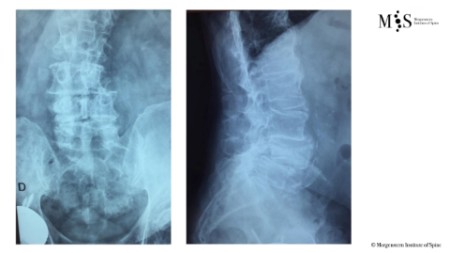

Estabilització percutània de fractures vertebrals inestables

En casos de fractures vertebrals complexes, inestables, comminutes, etc. es requereix una estabilització addicional de la fractura mitjançant una artròdesi percutània, i en alguns casos en els quals hi ha compromís neurològic, una descompressió del canal medul·lar. L’artrodesi percutània permet estabilitzar l’estructura compromesa de la columna vertebral i descarregar la càrrega del pacient sobre la fractura. Addicionalment se solen cementar les vertebres artròdesis i la fractura vertebral mitjançant cifoplastia.